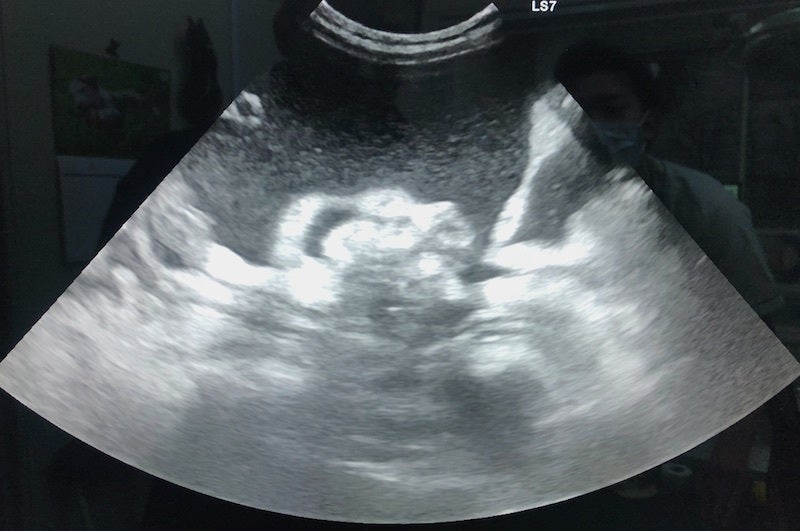

腹部エコー画像

FIPという診断を受けた時に、あらゆる手段を使いこの病気について調べました。動物病院の先生やネットで調べた結果、外猫・野良猫のほとんどが持っているコロナウイルスが突然体内で変異し、FIPウイルスになるということが分かりました。FIPウイルスは一度発症してしまうと元に戻ることはありません。原因はストレスのことが多いと言われており、ずら丸にストレスを与えてしまっていたと日々嘆くばかりです。現在の症状としては腹水・胸水の貯留、食欲減退、便秘、黄疸、脱水症状です。動物病院への通院で脱水症状については収まりを見せていますが、その他は改善の兆しが見えてきません。